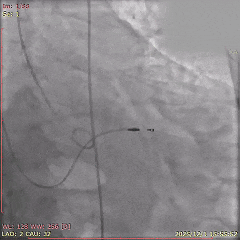

术中影像

初始造影确定无冠窦

瓣膜稳定释放至全展开

展开后造影,瓣膜位置可

多角度评估,确认瓣膜稳定

瓣膜脱钩后,无位移

最终造影,瓣膜位置可,无瓣周漏